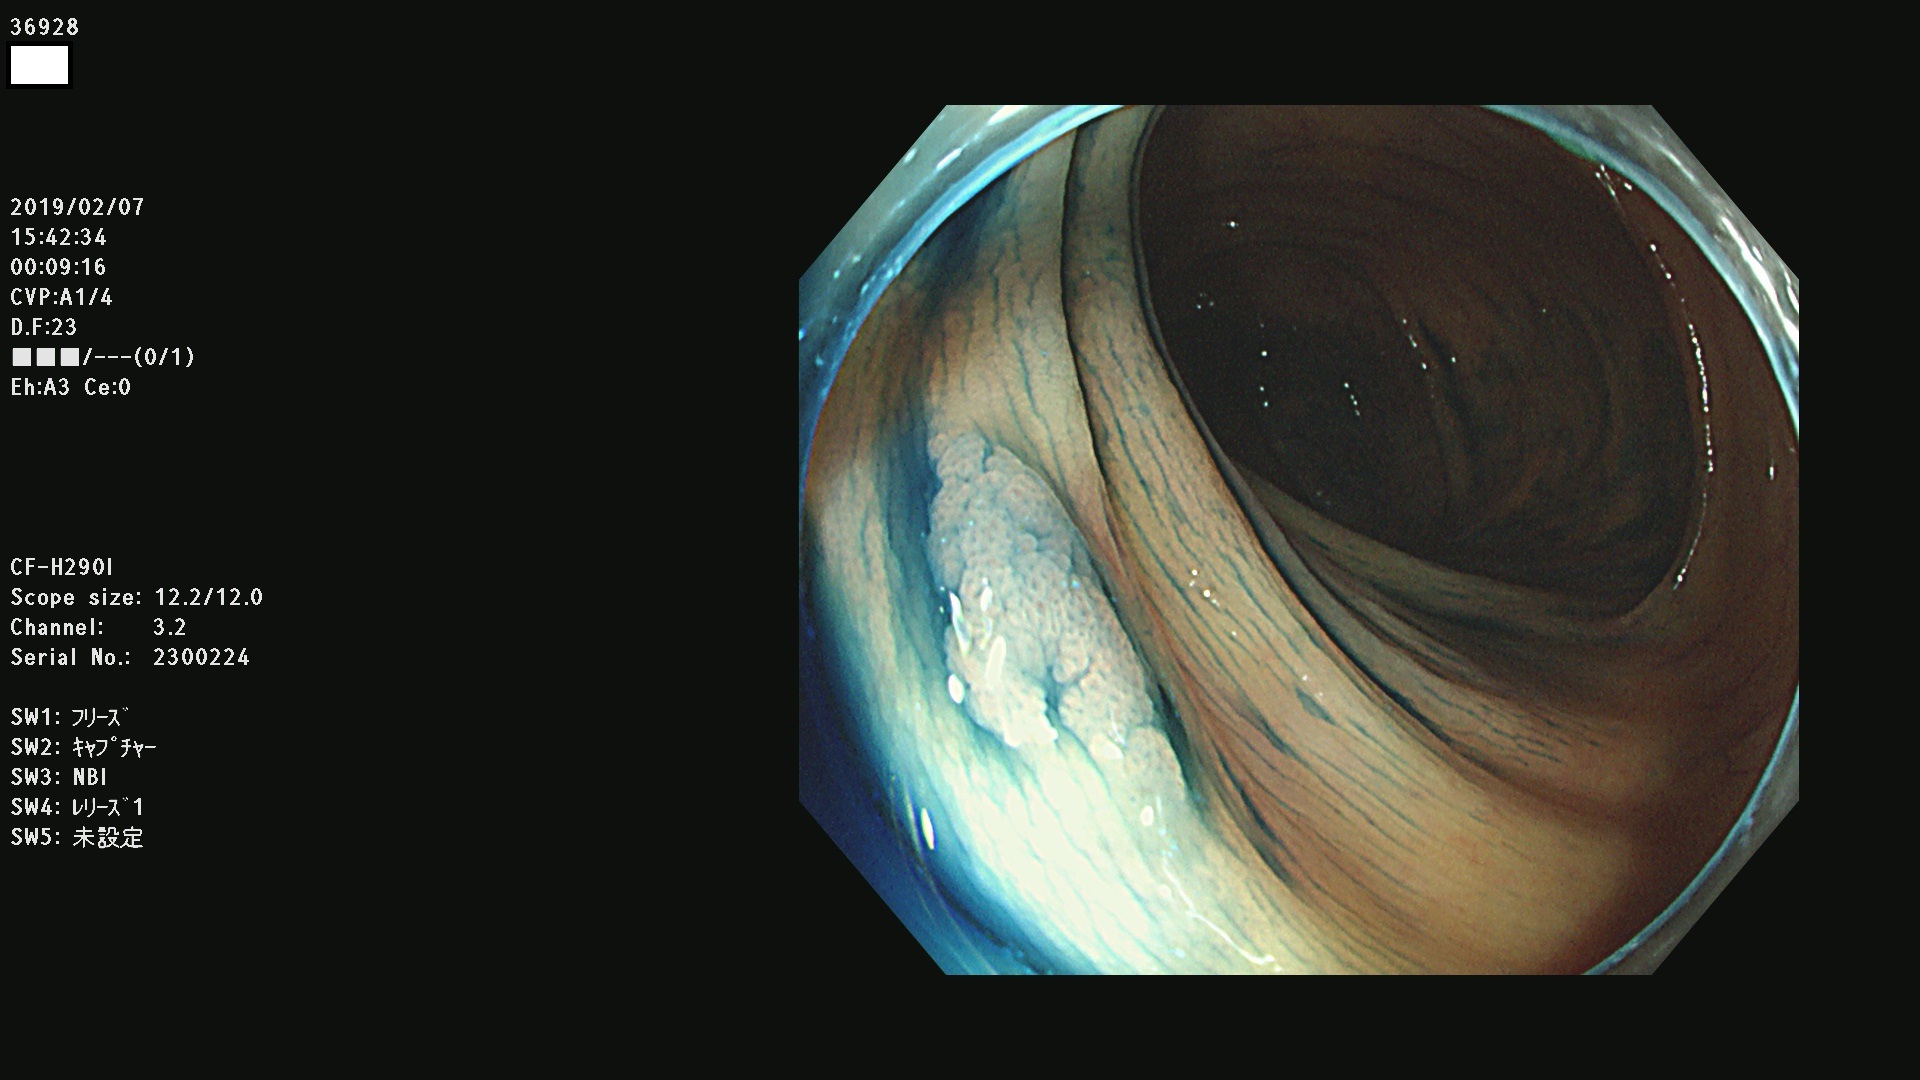

発見困難で危険性の高い平坦型病変(上記100名より抽出) ![]()